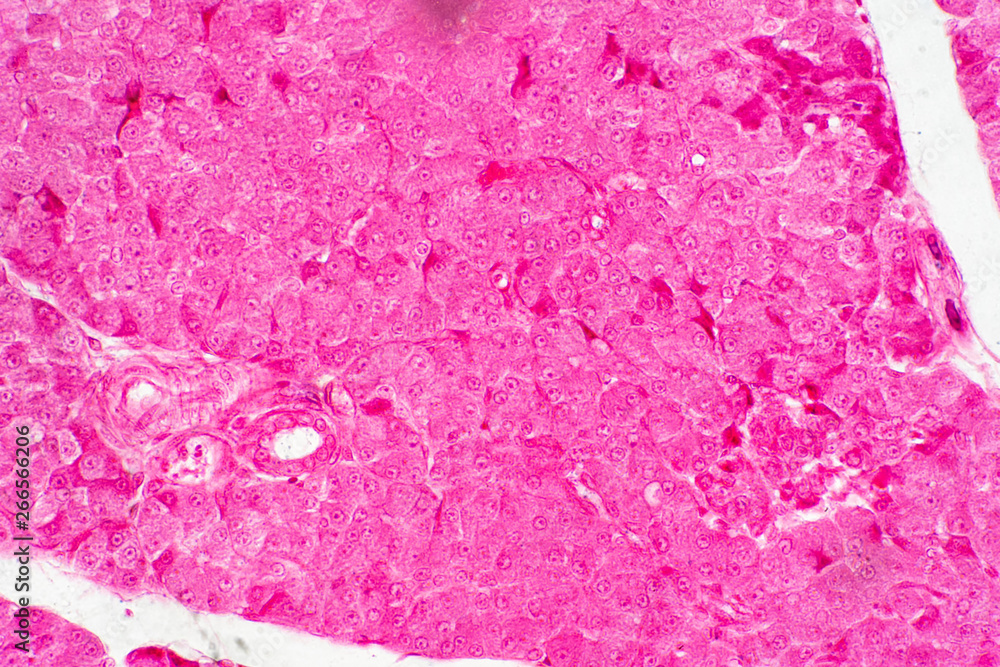

Human Liver Tissue Under Microscope View for Education Histology Stock Photo Image of Liver Tissue Histology Parenchyma, which is represented by hepatocytes; Sheets of connective tissue divide the liver into thousands of small units called lobules. The liver, the largest organ in the body, plays a major role in the uptake, storage and distribution of nutrients. The liver parenchyma or functional tissue of the liver is organized into thousands of hepatic lobules, which have a dual. Liver Tissue Histology.

In Depth View of Liver Tissue Histology Image in High Detail Stock Photo Image of biology Liver Tissue Histology The liver parenchyma or functional tissue of the liver is organized into thousands of hepatic lobules, which have a dual blood supply that comes from terminal branches of the hepatic portal vein and. Sheets of connective tissue divide the liver into thousands of small units called lobules. The liver consists of the following major histological components: It also maintains blood. Liver Tissue Histology.